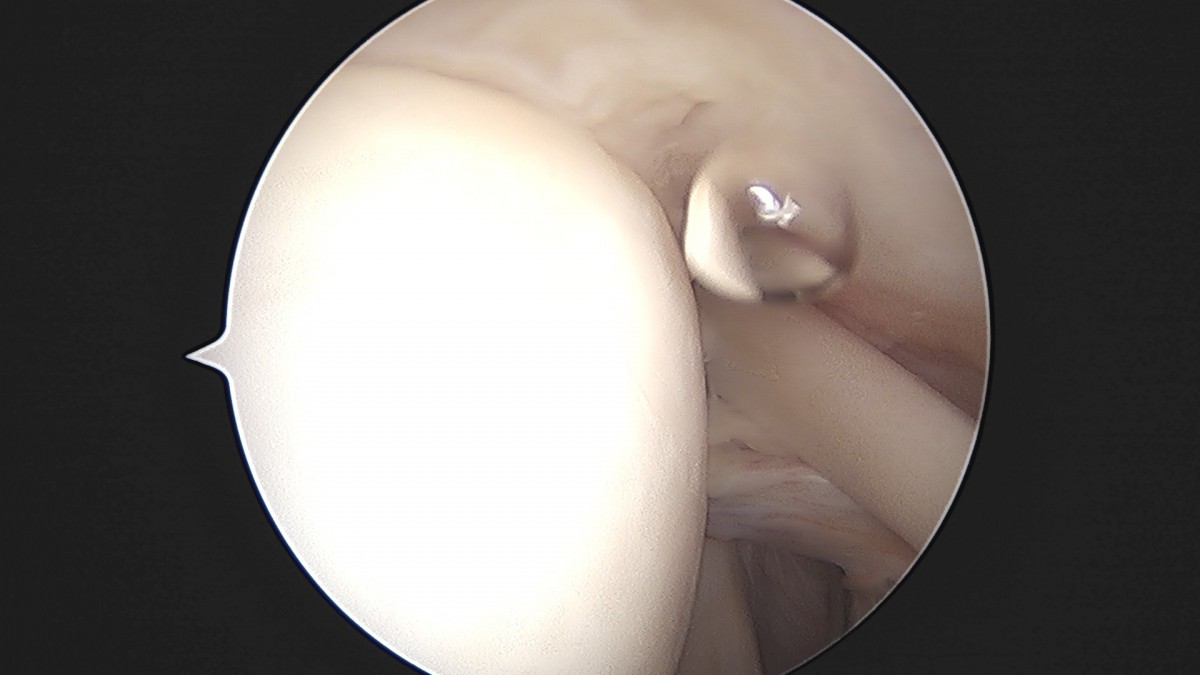

정지영원장님 어깨 관절낭 이완술 이상O 환자

dae765e4d9ac96aee867c9d6292d8784_1758009481_6661.jpg